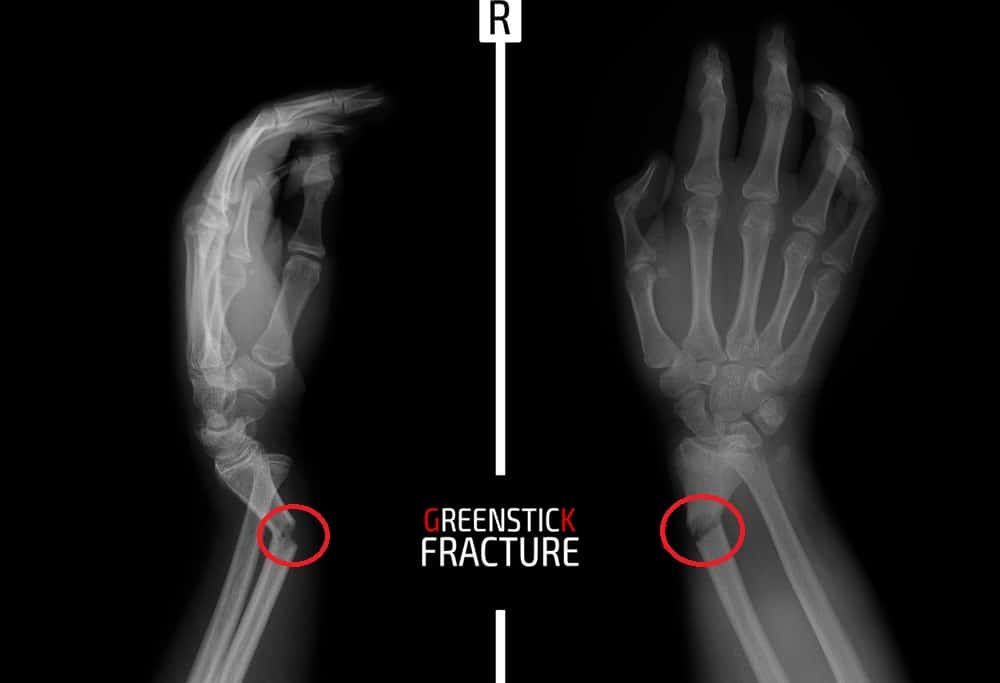

ग्रीनस्टिक फ्रैक्चर हड्डियों से संंबंधित समस्या है। जिसमें हड्डियां मुड़ जाती हैं और टूट जाती हैं। लेकिन, हड्डी दो भागों में टूट कर अलग नहीं होती है। इसलिए इसे इंकम्पलिट फ्रैक्चर भी कहते हैं। हरी छड़ी को तोड़ा जाता है तो वह मुड़ जाती है लेकिन, टूटती नहीं है। उसी आधार पर इस समस्या का नाम ग्रीनस्टिक फ्रैक्चर पड़ा है। इसे पार्शियल फ्रैक्चर भी कहते हैं।

- एक्स-रे (X-rays)- एक्स-रे से ग्रीनस्टिक फ्रैक्चर की स्थिति को समझा जाता है। इसे ठीक होने में एक सप्ताह या एक महीने तक का वक्त लग सकता है।